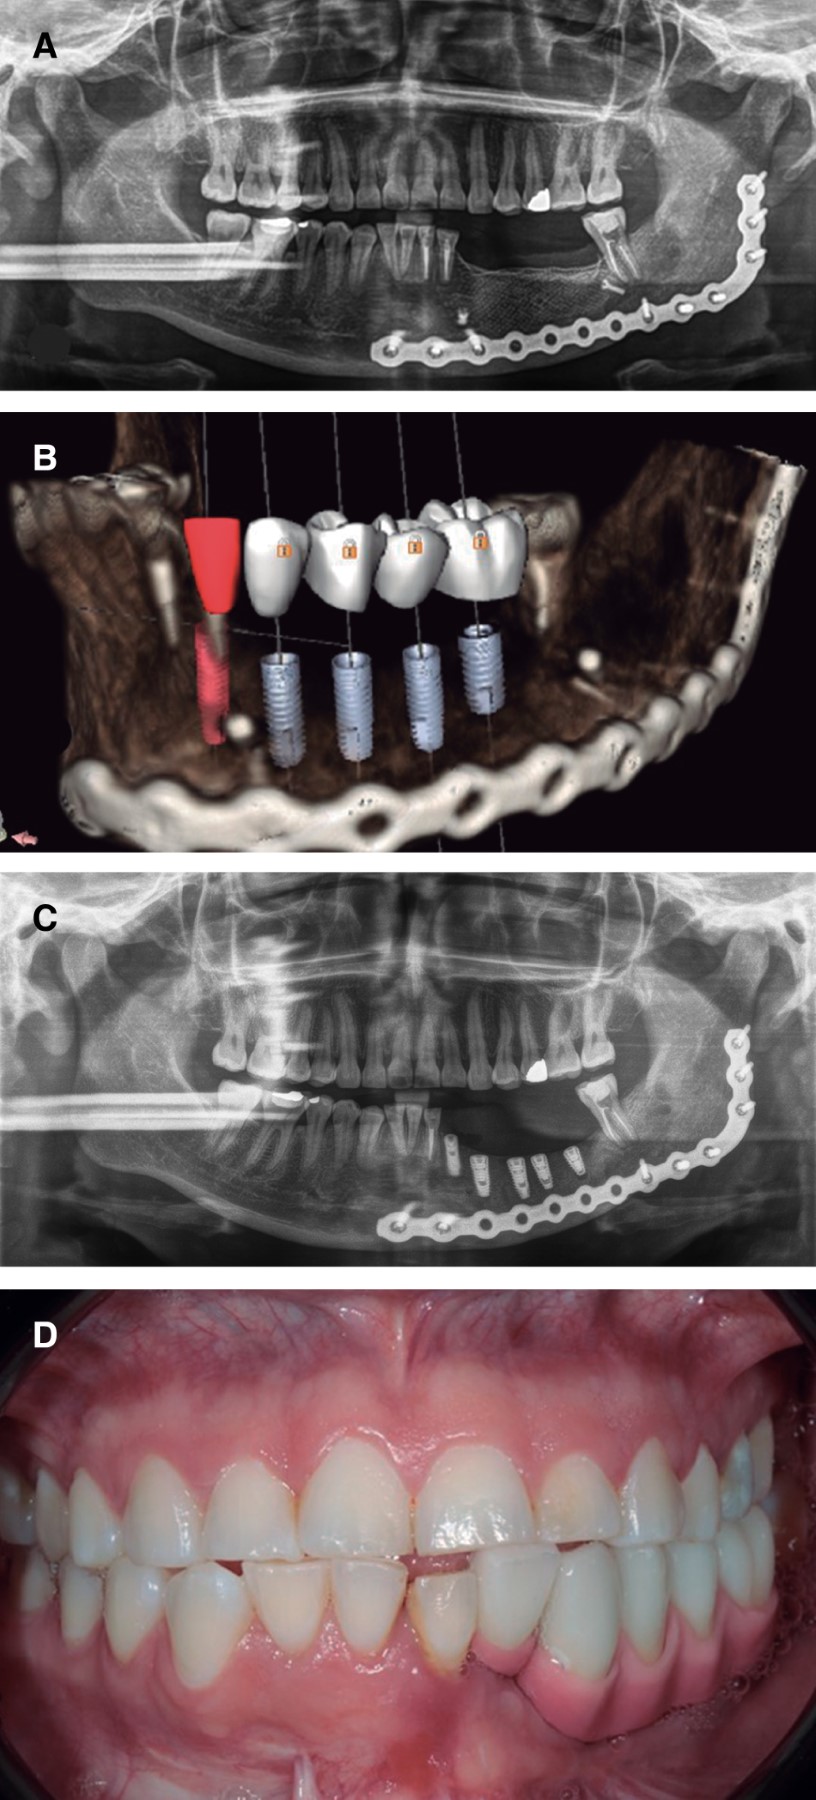

Las lesiones híbridas se consideran una patología rara que presenta elementos de diferentes entidades, cada una de las cuales tiene una categoría tumoral. En la actualidad hay menos de diez casos notificados de lesiones híbridas que muestran la asociación de una lesión central de células gigantes y un fibroma osificante. Dado que un protocolo de tratamiento para este tipo de patologías no está bien establecido en la literatura, presentamos un caso de manejo integral, incluyendo la rehabilitación, basado en la revisión de la literatura. Se trata de una paciente de 31 años con un diagnóstico inicial de lesión central de células gigantes en el cuerpo mandibular izquierdo, que fue tratada con triamcinolona intralesional, sin encontrar respuesta tras seis semanas de tratamiento, por lo que decidimos realizar una resección en bloque de la lesión y la reconstrucción simultánea con un injerto libre de cresta ilíaca anterior, obteniendo un resultado histopatológico definitivo de lesión híbrida (lesión central de células gigantes más fibroma osificante), posteriormente se realizó una rehabilitación protésica implantosoportada. En los casos de lesiones híbridas, consideramos que el manejo quirúrgico es adecuado, dado el comportamiento particular de dicha entidad que no responde adecuadamente al manejo farmacológico, recomendamos evitar el uso de medicamentos antirresortivos ya que perjudicaría el resultado de un tratamiento quirúrgico y reconstructivo posterior.

Figura 2